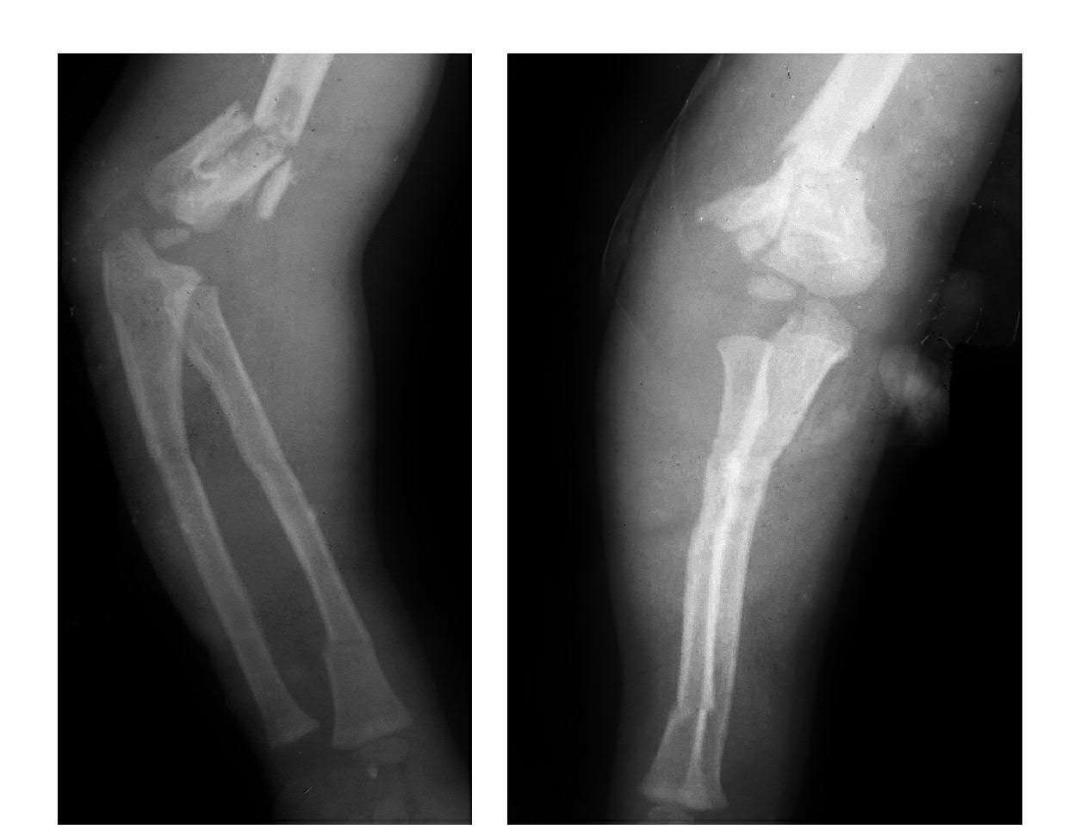

肘关节脱位与骨折脱位

肘关节后脱位

例1:肘关节过伸性半脱位。

例2:肘关节过伸性半脱位并肱骨小头外缘骨折。

例3:肘关节后侧脱位。

例4:肘关节后外侧脱位。

例5:肘关节后内侧脱位合并滑车后缘骨折。

例6:肘关节后外侧脱位合并外髁劈裂骨折。

例7:肘关节后外侧脱位并桡骨头劈裂骨折,致肱骨小头将桡骨头骨块推向肘关节内前侧。

例8:肘关节后侧脱位并桡骨头外侧关节面骨折与尺骨冠状突骨折,致该骨块移向肘关节内下方。